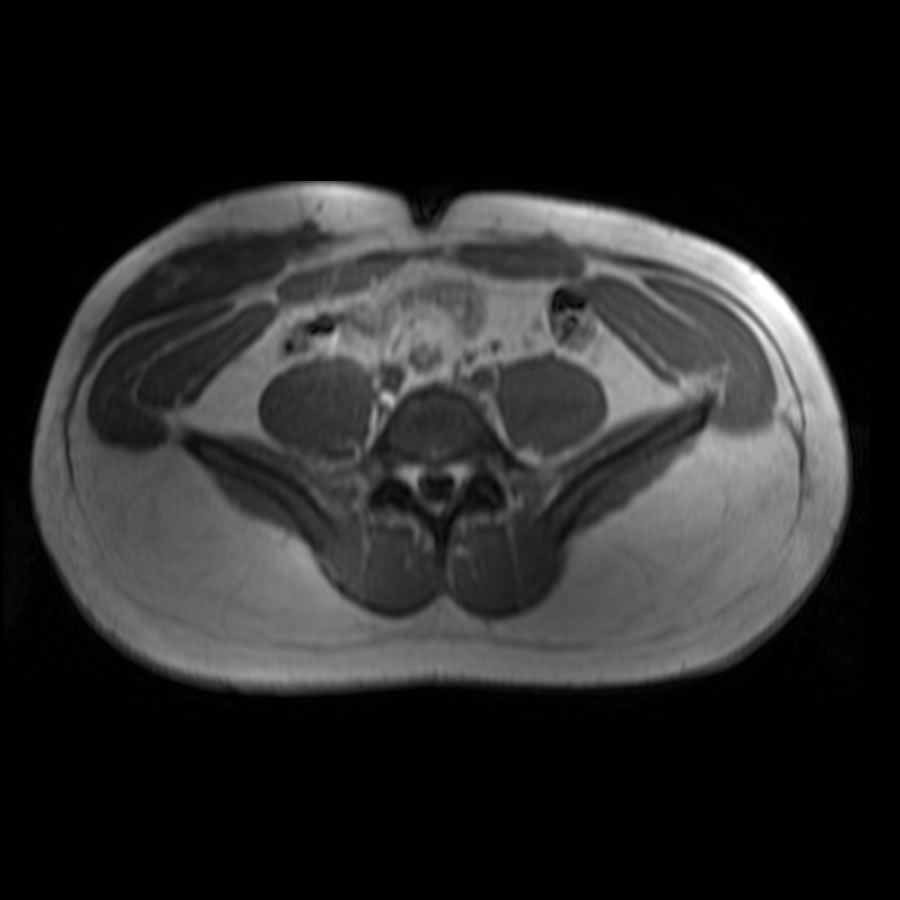

Octubre 2022. Sanatorio Allende Paciente masculino, 32 años que consulta por tumoración a nivel de partes blandas localizado en flanco y FID.